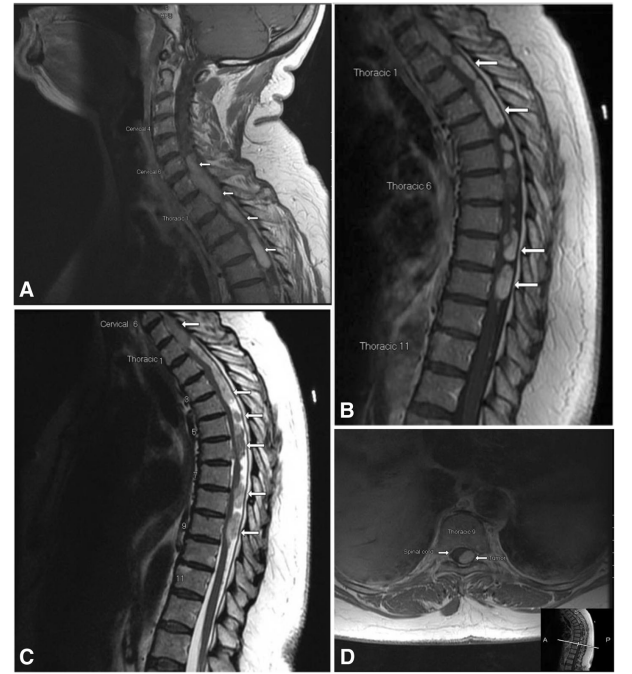

原發(fā)性、多灶性硬膜內(nèi)髓外毛細(xì)胞星形細(xì)胞瘤治療案例一則

毛細(xì)胞星形細(xì)胞瘤是一種低級(jí)別的中樞神經(jīng)系統(tǒng)腫瘤,硬膜內(nèi)髓外毛細(xì)胞星形細(xì)胞瘤獨(dú)自于原發(fā)實(shí)質(zhì)內(nèi)腫瘤的成人患者,因此相對(duì)很少被報(bào)道...